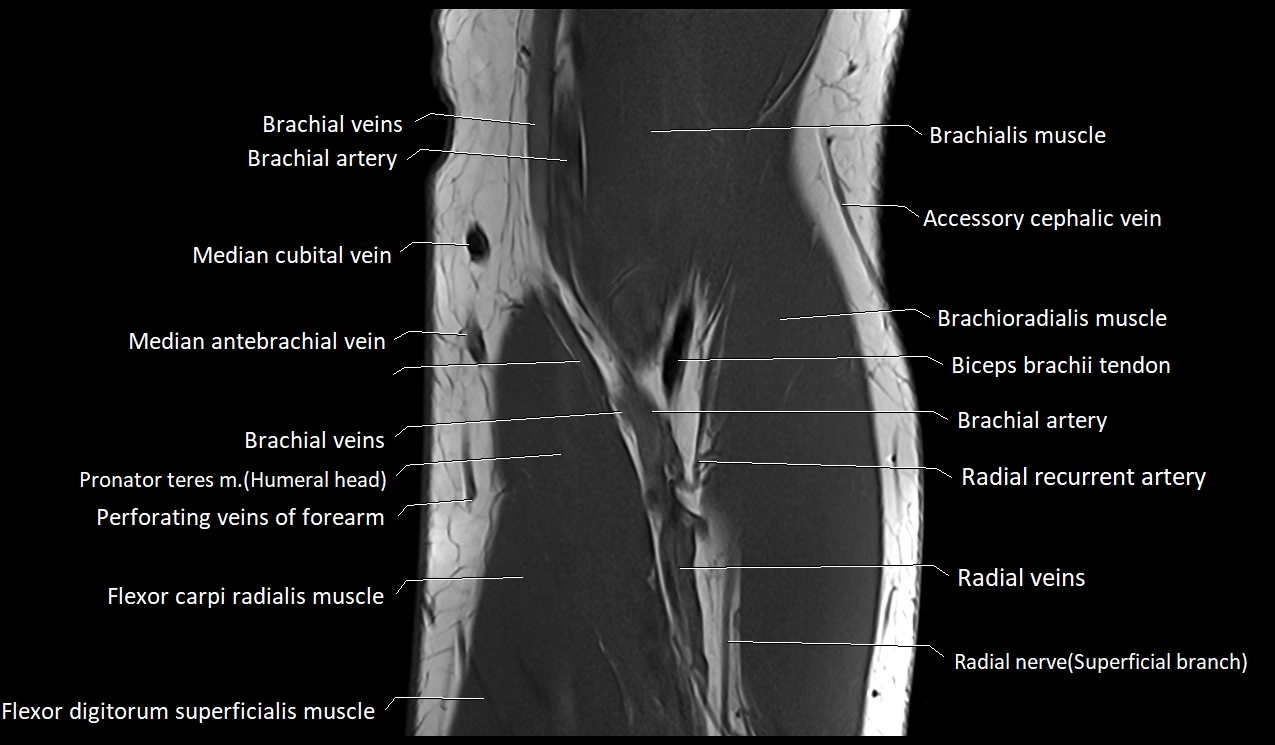

MRI image

image